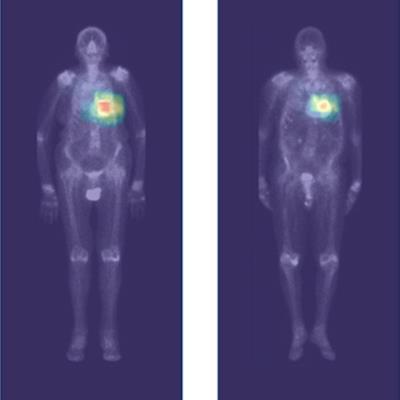

AI may help diagnose cardiac amyloidosis on whole-body scintigraphy #radiology #ImagingAI #NuclearMedicine buff.ly/42bzp6t

AI may help diagnose cardiac amyloidosis on whole-body scintigraphy #radiology #ImagingAI #NuclearMedicine buff.ly/42bzp6t